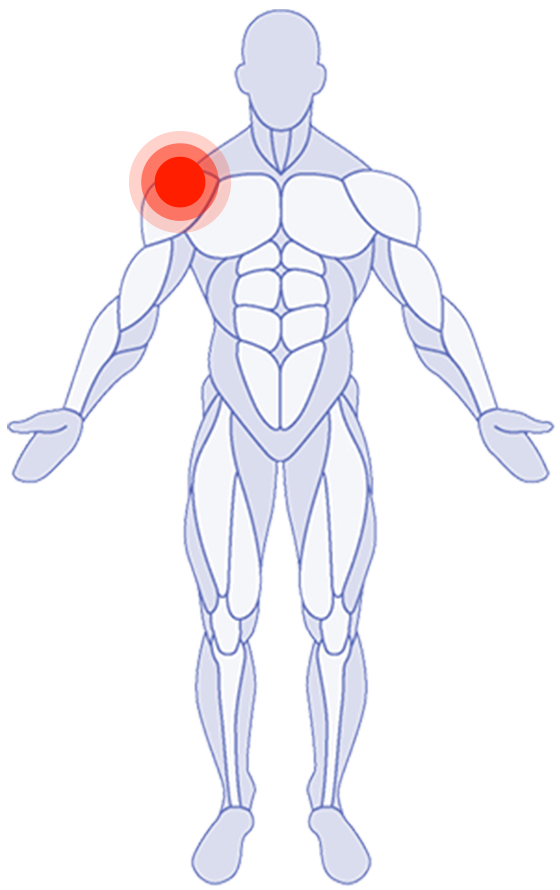

Where do you need attention?